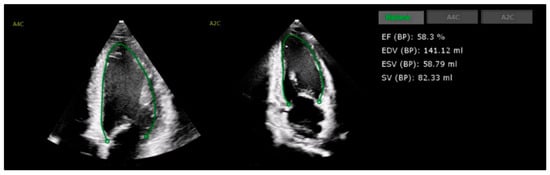

4.1. Left Ventricular Systolic Function

- Papadopoulou, S.L.; Dionysopoulos, D.; Mentesidou, V.; Loga, K.; Michalopoulou, S.; Koukoutzeli, C.; Efthimiadis, K.; Kantartzi, V.; Timotheadou, E.; Styliadis, I.; et al. Artificial intelligence-assisted evaluation of cardiac function by oncology staff in chemotherapy patients. Eur. Heart J. Digit. Health 2024, 5, 278–287. [Google Scholar] [CrossRef] [PubMed]

- Jiang, J.; Liu, B.; Li, Y.W.; Hothi, S.S. Clinical service evaluation of the feasibility and reproducibility of novel artificial intelligence based-echocardiographic quantification of global longitudinal strain and left ventricular ejection fraction in trastuzumab-treated patients. Front. Cardiovasc. Med. 2023, 10, 1250311. [Google Scholar] [CrossRef]